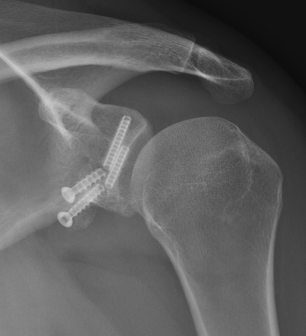

Case 1: Failed Latarjet